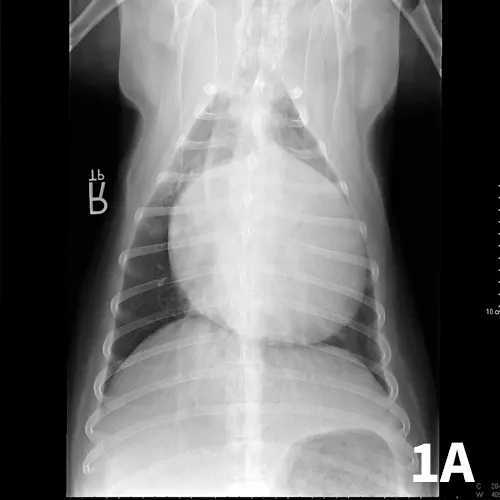

Diagnosis may be based on clinical signs, thoracic radiographs documenting a globoid cardiac silhouette (Figure 1), or ultrasonography (Figure 2). If possible, a complete cardiac ultrasound examination should be performed before pericardiocentesis, as the effusion will help delineate a mass.

Ventrodorsal (A) and right lateral (B) thoracic radiographs showing a globoid heart.